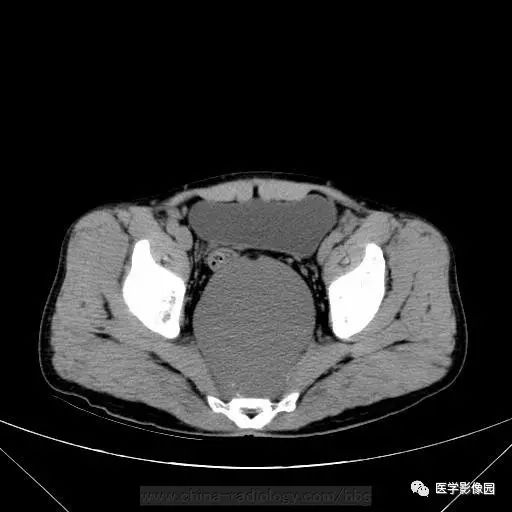

男,46岁,下腹不适一周。

影像学表现:盆腔内直肠后方骶椎骨前方囊性肿块,内见斑点状钙化灶,增强无明显强化。

诊断结果:支气管源性囊肿

一般发生于后腹膜上部多见,发生在骶尾部的少见。CT多表现为膈下圆形或类圆形,界限清晰 低密度囊肿,一般上极较高,可达膈下。因囊液含有蛋白,CT值可较高,达50~60Hu。因其组成成份多不,且可钙化。故有时和畸胎瘤样囊肿难以区别!